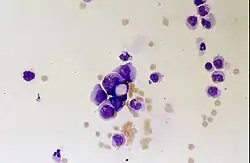

Linfomas primários do SNC

O linfoma primário do sistema nervoso central é responsável por cerca de 2 por cento para 3 por cento de todos os tumores cerebrais em pacientes com um sistema imunológico normal. Ocorrem mais frequentemente em homens com mais de 55 anos até 60 anos acima. Quase metade de todos os linfomas ocorrem em pacientes com mais de 60 anos e cerca de um quarto em pacientes com mais de 70 anos. anos acima. A incidência parece aumentar com a idade, mas a razão ainda não é clara. Pacientes com sistema imunológico enfraquecido correm maior risco de desenvolver linfoma do SNC, portanto, aqueles que tiveram um transplante de órgão têm uma imunodeficiência congênita ou doença autoimune ou estão infectados com o vírus da imunodeficiência humana. Os linfomas cerebrais associados ao HIV estão associados ao vírus Epstein-Barr, particularmente em pacientes com contagens de linfócitos CD4 abaixo de 500 células por milímetros cúbicos no sangue. A maioria dos linfomas do SNC são linfomas difusos de grandes células B.

Os pacientes sofrem de uma variedade de sintomas característicos de uma lesão maciça focal ou multifocal. A RM geralmente mostra tumores com realce homogêneo de contraste dentro da substância branca periventricular profunda. Multifocalidade e realce não homogêneo são típicos para pacientes com sistema imunológico enfraquecido. A análise do linfoma do SNC é extremamente importante no diagnóstico diferencial das neoplasias cerebrais. Ressalta-se que a administração de corticosteróides pode levar ao desaparecimento completo do realce, dificultando o diagnóstico das lesões. Consequentemente, se o linfoma do SNC for considerado no diagnóstico diferencial, os corticosteróides devem ser evitados, a menos que o efeito de massa cause um problema sério e imediato no paciente.

A biópsia da lesão suspeita é crucial. Ao contrário do linfoma sistêmico de grandes células B, no qual tanto a quimioterapia quanto a radioterapia são eficazes e o tratamento de lesões localizadas é curativo, o linfoma do sistema nervoso central geralmente responde à terapia inicial, mas depois recorre. Assim como no linfoma sistêmico, o papel da cirurgia limita-se principalmente à obtenção de amostras de tecido apropriadas para o diagnóstico.

No passado, a radioterapia era administrada em todo o cérebro (panencefálico). A sobrevida mediana é de cerca de 12, mesmo com lesões localizadas Meses. A recorrência geralmente afeta o local da lesão anterior, bem como outras regiões. As respostas à quimioterapia são mais promissoras. Ensaios clínicos nos quais o metotrexato em altas doses foi usado como primeiro tratamento e a radioterapia foi adiada até o momento da recidiva ou progressão mostraram melhor sobrevida global do que a radioterapia isolada. Ainda mais eficaz foi a combinação de metotrexato, vincristina, procarbazina, metotrexato intratecal, citarabina e radioterapia panencefálica e citarabina, ou o uso de quimioterapia intra-arterial com metotrexato intra-arterial, ciclofosfamida injetada por via intravenosa e etoposídeo após modificação do sangue- barreira cerebral com manitol. A sobrevida mediana na terapia com metotrexato foi de 24 até 40 meses muito maior do que com radioterapia isolada (intervalo de 24 até 40 meses). Em alguns casos, a radioterapia é utilizada apenas para recidivas quando há uma regressão inicial com a quimioterapia. Casos de longa sobrevida também foram relatados sem radioterapia.

A radioterapia panencefálica está associada a um alto risco de desenvolver demência ou leucoencefalopatia. Esse risco pode ser reduzido desenvolvendo estratégias eficazes de controle do tumor que evitem a radioterapia panencefálica. A terapia inicial para pacientes com sistema imunológico comprometido é reduzir as causas da imunossupressão. O prognóstico para esses pacientes geralmente é pior do que para pacientes que têm um sistema imunológico normal. Devido a infecções tumorais concomitantes e uma condição física geralmente abaixo do ideal, a quimioterapia muitas vezes não pode ser realizada nesses pacientes imunossuprimidos. Tal como acontece com outros tumores cerebrais, a resposta aos tratamentos depende da idade e da condição física.